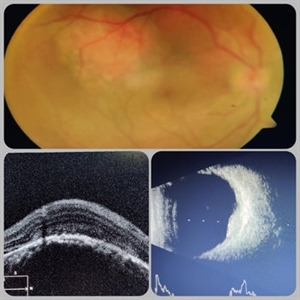

Circumscribed Choroidal Hemangioma

Circumscribed Choroidal Hemangioma

Jul 3 2020 by Dhaivat Shah

A 30-year-old young male presented with drop in vision in right eye since 1 year (6/60). Fundus examination revealed choroidal hemangioma superotemporal to macula. Choroidal hemangioma is an unusual benign vascular tumor of the choroid. It can be circumscribed solitary or diffuse tumor with the later having other systemic associations. Circumscribed choroidal hemangiomas (CCHs) are usually unilateral, unifocal hamartomatous vascular tumor affecting people in second to fourth decade. It appers as round to oval, orangish-red mass in posterior pole with smooth homogenous surface mostly present in macular and peripapillary area. Hyperopic shift is seen in sub-foveal tumors in contrast to para-foveal ones which are usually asymptomatic or present with metamorphopsia or photopsia and diminished vision secondary to exudative retinal detachment. B-scan shows highly reflective tumor without any shadowing or acoustic solidity with high anterior A scan spike. EDI-OCT here depicts a smooth gently sloping choridal mass with compressed choriocapillaries and enlarged medium and large choroidal vessels. Over a period of time structural abnormalities of the outer retina can be visualised. Ancillary testing using Fluorescein Angiography shows lacy hyper-fluorescence during early arterial phase followed by increased hyper-fluorescence due to progressive profuse leakage from pin point foci during arterial and venous phase. Indocyanine green angiography shows lacy diffuse fluorescent tumor in early phase followed by hypo-fluorescent tumor due to dye wash out in late phase. Intrinsic auto-fluorescence is also seen in CCHs from lipofuscin and fresh sub-retinal fluid. Tumor is relatively hyper-intense with respect to vitreous in T1-weighted images in iso-intense in T2-weighted images of MRI. Asymptomatic cases need no treatment, while patients showing vision loss with presence or absence of exudative retinal detachment can be treated with photodynamic therapy which is preferred treatment due to site specific action. Selective occlusion of choroidal neovascularization can be achieved while the neurosensory retinal layers and Bruch membrane are almost unaffected, leaving retinal function intact. Green or rarely red wavelength laser photocoagulation is used to create a chorioretinal adhesion and resolve the SRF. Other treatment modalities include Transpupilary thermotherapy, external beam irradiation, proton beam therapy, brachytherapy and gamma knife.

Photographer: Miss Deepika Nagle

Imaging device: Zeiss

Condition/keywords: B scan ultrasound, choroidal hemangioma, fundus photograph, optical coherence tomography (OCT), photodynamic therapy